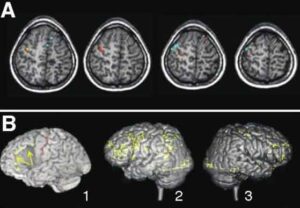

Uno studio, condotto utilizzando la risonanza magnetica funzionale, ha mostrato come due distinte regioni cerebrali che regolano le emozioni e...